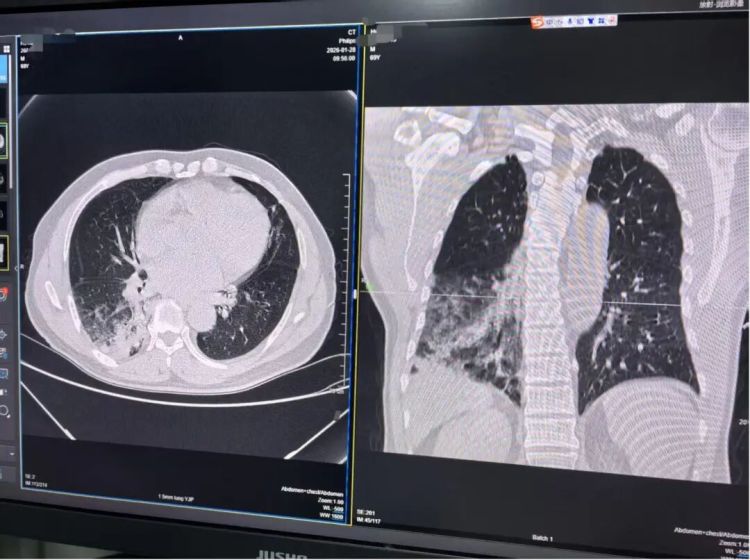

胡爷爷的肺部CT结果